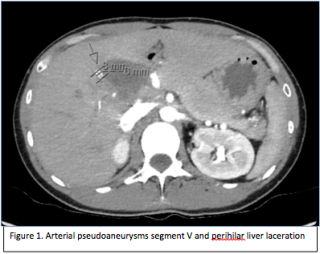

Case presentation

A 72-year-old male patient presented with acute onset of thoracic and abdominal pain, additionally complaining of light-headedness and cold sweats. The medical history was unremarkable regarding previous trauma or infections, but the patients was recently diagnosed with a kidney mass. The patient was hypotensive, tachycardic, with cold peripheral extremities and tenderness in the epigastrium. Laboratory investigations showed mild anaemia and leucocytosis, impaired renal function, and high lactate. Ultrasonography suggested free fluid in the Morison’s pouch, a mass of the left kidney and inhomogeneous splenic tissue, confirmed by CT angiography, which revealed a hematoma of the spleen with signs of ongoing bleeding and free fluid in the abdominal cavity.

After initial stabilization with blood transfusions and phenylephrine, an endovascular approach was planned. However, the patient developed hypovolemic shock prior to the procedure, indicating urgent explorative laparotomy. After the splenic hilum was initially clamped, splenectomy was performed, resulting in hemodynamic stabilization. Subsequent exploration of the abdomen revealed peritoneal nodules and a tumour of the left kidney. Peritoneal biopsies were taken and showed a papillary renal cell carcinoma. The patient was referred for further diagnostic and treatment to the oncology department to receive chemotherapy.